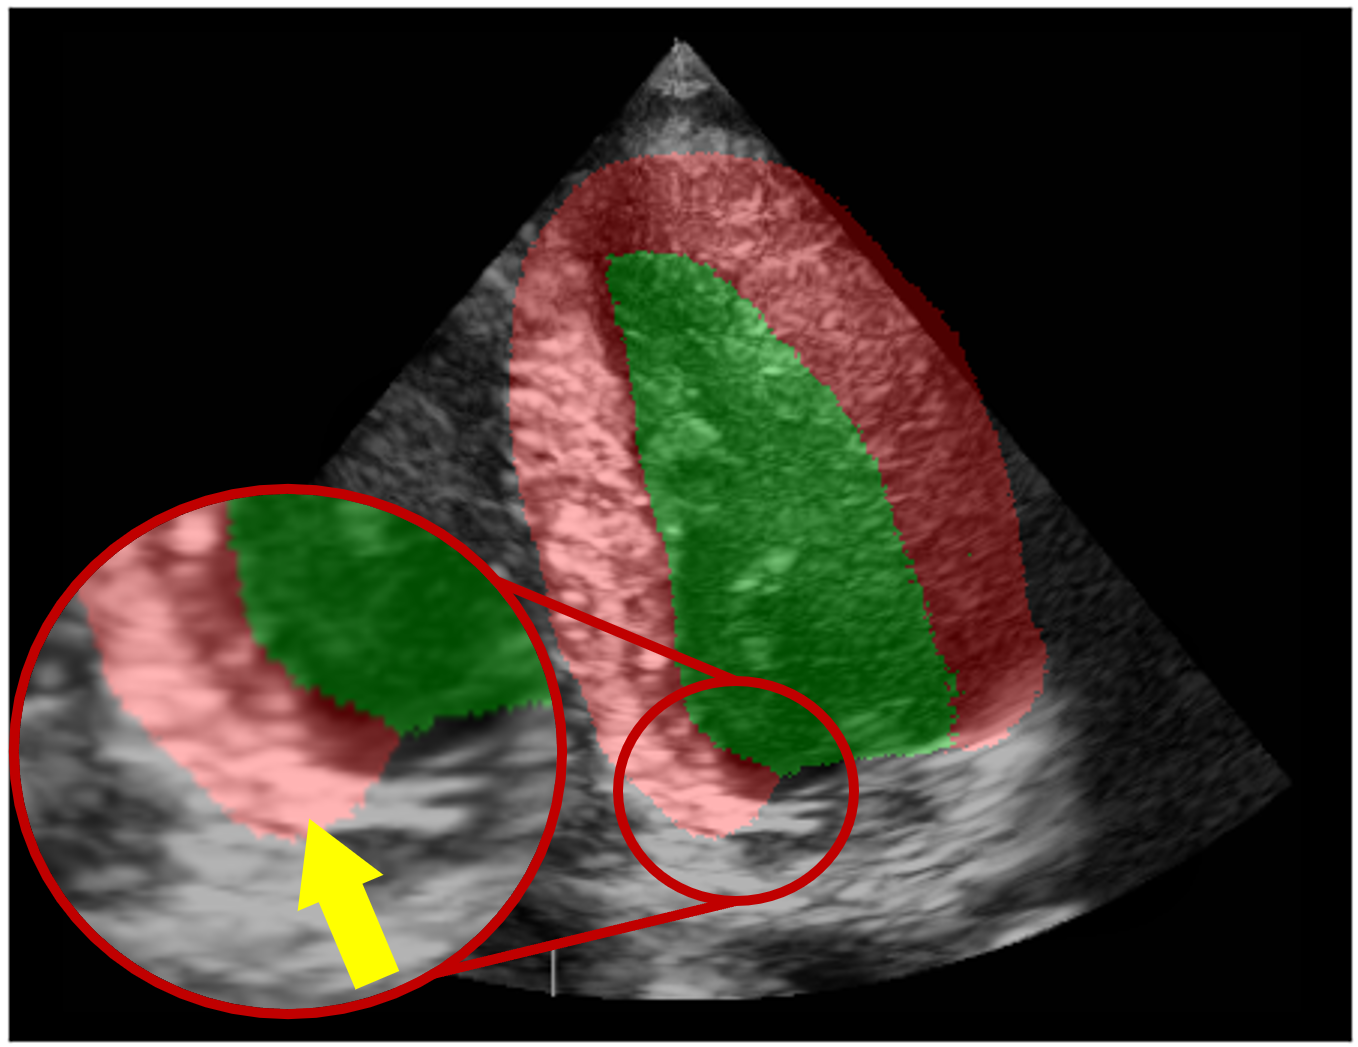

Figure 2: Example of a segmentation frame (a) and reward maps highlighting errors. The anatomical reward (b) from rψ𝐴𝑁𝐴𝑇r_{\psi}^{\mathit{ANAT}} shows general segmentation issues such as the misshapen apex, while the landmark reward (c) from rωLMr_{\omega}^{LM} highlights errors in mitral valve alignment. The final reward map (d), obtained with min-based fusion, illustrates a localization error at the left mitral valve commissure: the segmentation places it inside the ventricle (red circles), whereas the correct location is indicated by the yellow arrow. (e) illustrates ground truth error maps for the validated landmark (LM) subset, and (f) shows the fused reward map with the temporal penalty applied. Video of full sequence and rewards available in supplementary material.

A key strength of RL and, by extension, of the segmentation RL formalism, is its flexibility in optimizing any non-differentiable objectives. This allows to incorporate multiple reward components to specifically address segmentation errors. Accordingly, we define a set of rewards RR used for 3D segmentation RL training, where each individual reward rr corresponds to a pixel-wise error map providing feedback on a distinct type of segmentation errors. Rewards are categorized as adaptive, which evolve and improve at each iteration of the RL framework, or static, which are pre-trained in step 0 and remain fixed throughout the domain adaptation process.

Basing the fusion mechanism on the minimum operator ensures that the policy is corrected based on the most severe error at each pixel, maximizing its ability to address critical segmentation mistakes.

As shown in Fig. 2(c), we set the mitral valve commissure as the primary landmark that segmentations must accurately follow to remain consistent with the image sequence. These structures represent the junction between the mitral valve leaflets and the annulus. In apical two- and four-chamber echocardiographic views, these landmarks are generally visible on the images and correspond to the base of the segmentation mask, at the two points where the left ventricle, myocardium and background classes coincide. Aligning precisely with the mitral valve commissure is especially important for downstream tasks such as cardiac tracking, which rely on the accuracy of segmentations.